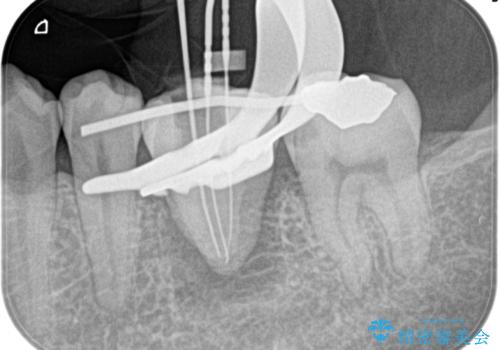

移植歯はアンキローシス(歯と歯槽骨の間の歯根膜がなく、歯の根と骨が結合している状態)するリスクがあります。

アンキローシスを避けるため、術中や術後管理に注意が必要です。